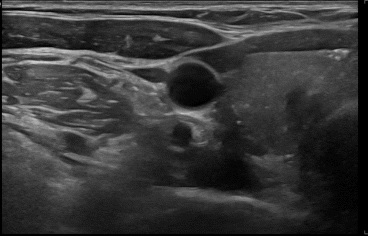

상기환자 외부검사이상소견으로 정밀검사위해 내원하신 40대 중반 여성분으로 갑상선 초음파 시행후 의심스러운 갑상선 우엽 결절 세포검사 진행후 갑상선암으로 진단되었습니다